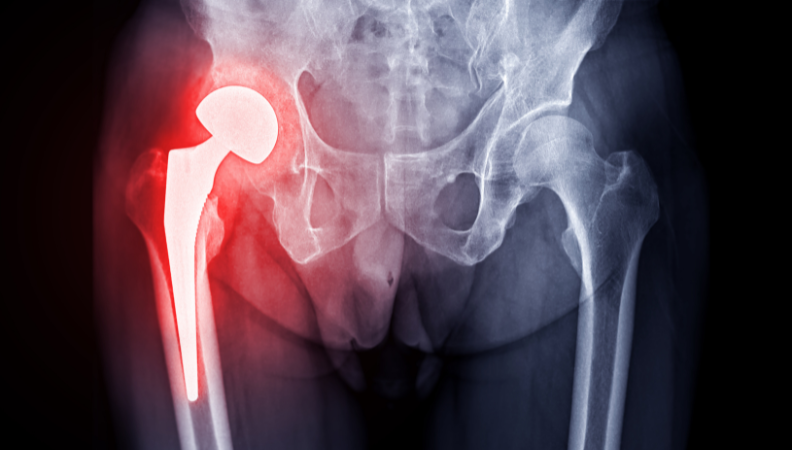

Total Hip Replacement (THR), also known as hip arthroplasty, is a surgical procedure in which a damaged or worn-out hip joint is replaced with an artificial implant. It is commonly recommended for patients with severe arthritis, hip fractures, or chronic hip pain that limits movement and daily activities.

- Total Hip Replacement